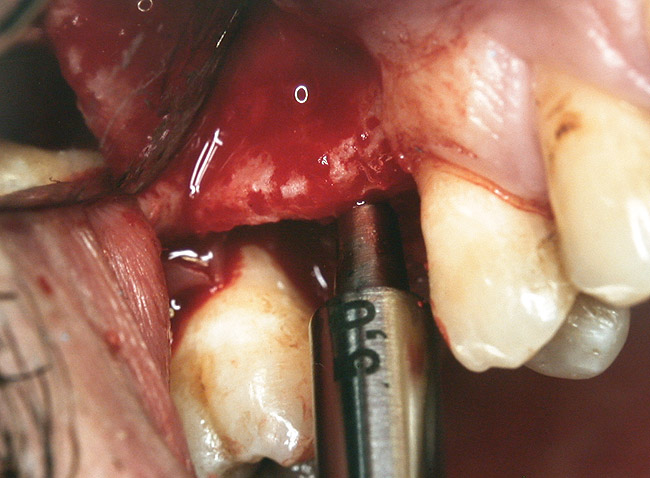

Case 2

A 55-year-old male was referred for implant placement and prosthetic rehabilitation in the area of tooth No. 15. The tooth had been extracted 4 years prior. The radiograph revealed inadequate bone height for implant positioning (Figure 6). It was decided to insert an implant that was 11.5 mm in length and 3.75 mm in diameter, performing a slight osteotomic maxillary sinus lift. A heterologous bone graft also was planned to obtain a larger sinus lift.

A full-thickness mucoperiosteal flap was raised, and alternating osteotomes were used to prepare the implant site. After achieving a length of 7 mm (Figure 7A and Figure 7B), heterologous bone graft was implanted and the osteotome sequence was repeated. The implant showed primary stability.

Figure 7A and Figure 7B Alternating osteotomes with variable conicity used to perform the alveolar remodeling in the area of tooth No. 15.

Figure 7b  Alternating osteotomes with variable conicity used to perform the alveolar remodeling in the area of tooth No. 15.

Figure 7b